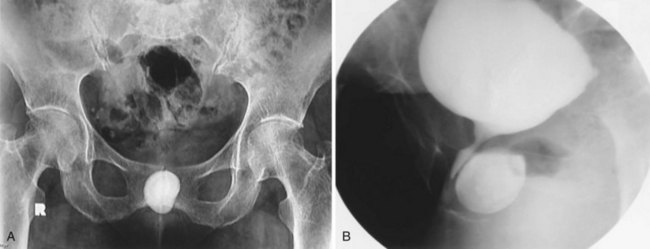

A bladder diverticulum may cause deviation with or without compression of the ipsilateral ureter. On intravenous urography, medial deviation of the pelvic ureter is most commonly seen; however, lateral deviation may also occur (Talner et al, 2000) (Fig. 78–5). Furthermore, a bladder diverticulum that encompasses the ureteral orifice may create a functionally shortened intramural ureteral segment and result in vesicoureteric reflux (see later discussion). In these patients, excision of the bladder diverticulum with ureteroneocystotomy may be necessary.

Figure 78–5 Bladder diverticulum with deviation of the ureter. This patient had a long history of recurrent urinary tract infections due to presumed prostatitis. A, 10-min film from the intravenous urogram demonstrating medial deviation of the pelvic ureter (arrow). B, Voiding image from the voiding cystourethrogram revealed a large, smooth-walled bladder diverticulum (D) emanating from the trabeculated bladder (B).